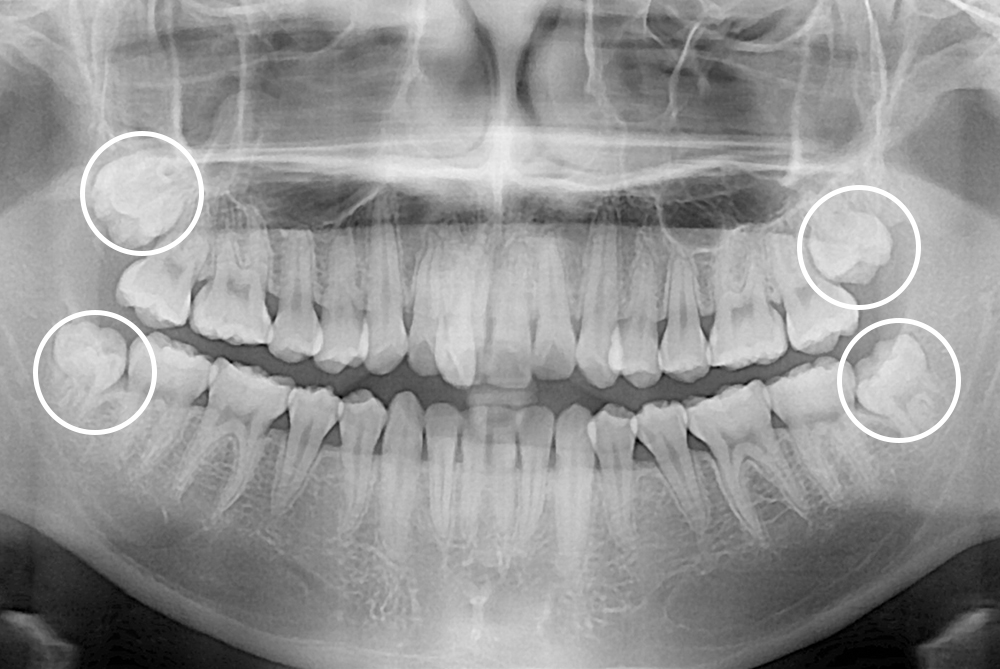

[사랑니] 매복 사랑니 발치

치료전 : 2019-01-17